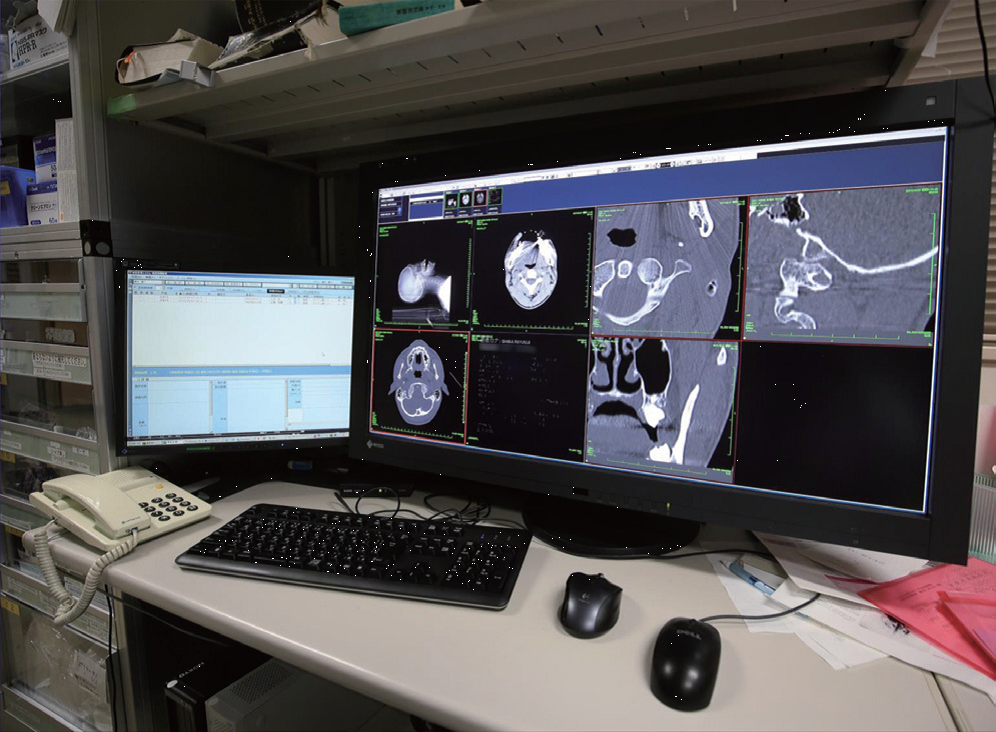

37インチ、4K、8メガカラー。

150cm幅の机上にも十分収まった。

2013年、PACSシステムを更新することになり、37インチ、4K、8メガカラーのRX840マルチモダリティモニタを導入した。この際、懸念したのは37インチというモニタのサイズだった。当時は23インチを使っており、37インチを机上に設置するのは難しいと思われたが、150cm幅の机に読影レポート用の19インチモニタと37インチを並べて設置することができた(図1)。